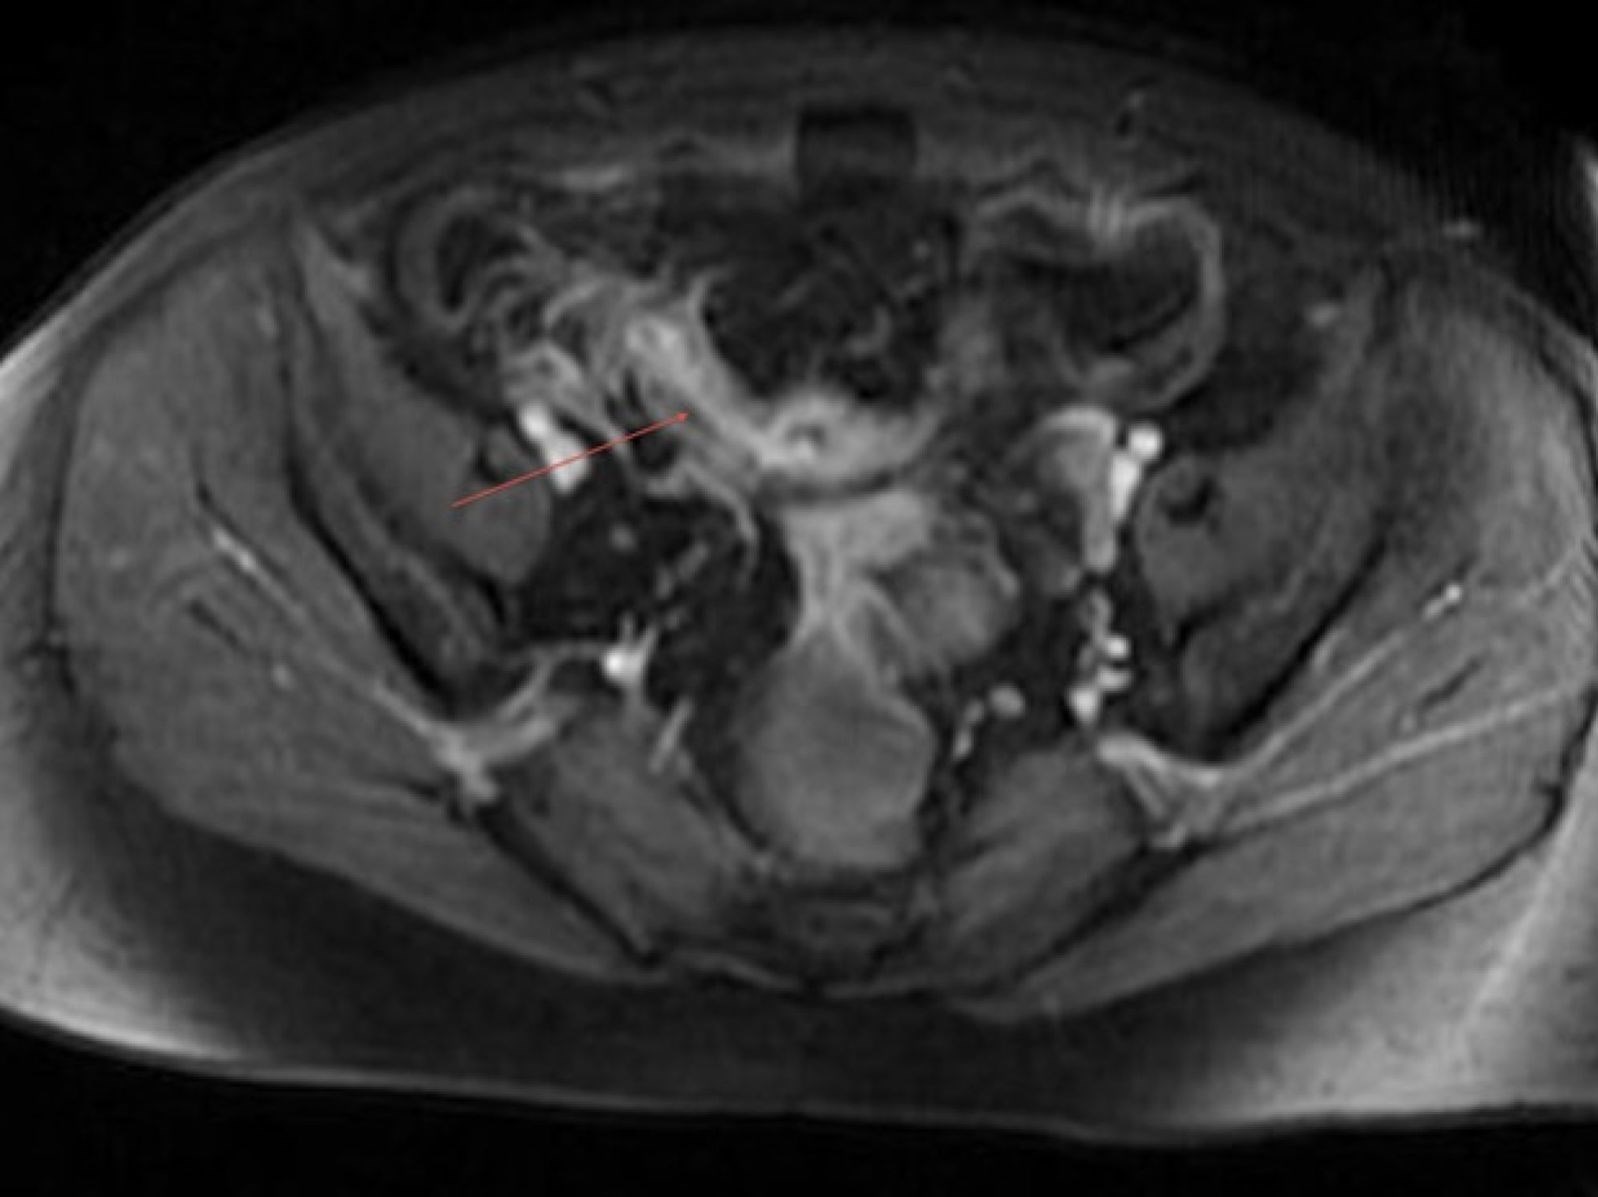

درد شدید بیمار در نهایت پزشکان را مجبور کرد که با جراحی سوراخی در شکم بیمار ایجاد کنند.سوراخی که در دیواره روده کوچک بیمار ایجاد شد اما پزشکان را با منظره عجیبی مواجه کرد.

در روده کوچک بیمار دو قطعه پلاستیکی مربوط به بستهبندی پلاستیکی یک سُس با نام تجاری معروف Heinz پیدا شد.

پزشکان در این رابطه گفتند که این قطعات بسته بندی پلاستیکی در بدن بیمار علائم بیماری کرون را تقلید میکرد و در تشخیص درست مشکل آنها را گمراه کرده بود.